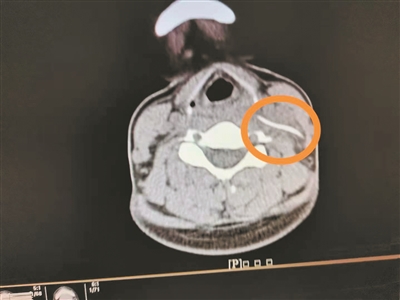

影像检查显示颈部异物。

4月1日,陈女士带女儿到南方医科大学第三附属医院就诊,想起自己颈部不舒服,就顺便到耳鼻咽喉科就诊,副主任医师曹庆硕接诊后,请患者平躺检查,此时陈女士感觉颈部更痛了,医生怀疑颈部有异物,于是进行了颈部CT平扫,果然发现左侧颈动脉鞘区有异物。

据耳鼻咽喉科主任田广永介绍,咽喉、食道异物临床上常见,但是,异物进入颈部肌肉间隙内这种情况还是比较少见的,比较容易误诊和漏诊。陈女士误吞的鱼刺直接刺破咽腔黏膜和周围肌肉进入颈部咽旁间隙内,而且位置较深,所以喉镜检查很难发现,行颈部CT才找到异物的位置,若异物刺穿颈动脉或静脉血管,那后果不堪设想。